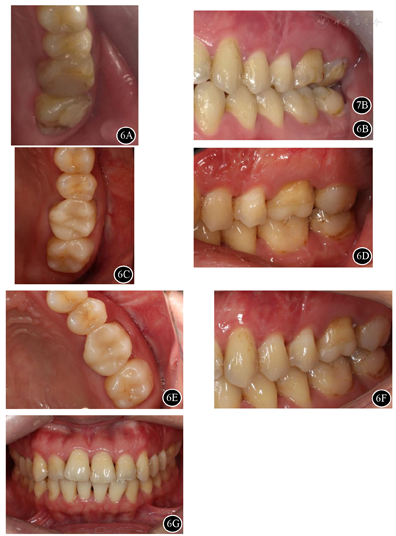

术后定期复查,无诉不适。口内检查:26叩(-),无明显松动,局部牙龈及黏膜未见明显异常(图6)。7B复查根尖片示26根尖区骨密度较术前明显增加(图7)。

面照;B:术后10个月26颊面照;C:术后4年26

面照;D:术后4年26颊面照;E:术后5年26

面照;F:术后5年26颊面照;G:术后5年牙列正面照

术后2年CBCT示:26根尖部分切除,形态平钝,根管倒充填致密;根尖区骨密度较术前明显增加,但其上方至左侧上颌窦底壁以及颊侧骨皮质仍见缺损(图8A、图8B)。术后4年与术后5年CBCT影像表现基本同术后2年(图8C,图8D,图8E,图8F)。

26根尖区骨密度较术前明显增加,但根尖区颊侧骨皮质连续性部分中断,根据Penn影像学分类属于有限愈合。一般认为,无临床症状,并且影像学分类为完全愈合或有限愈合者,可视为成功。故本病例最终评价为成功。其上方至左侧上颌窦底壁存在骨质缺损,考虑为左上颌窦炎行左上颌窦根治术的术后表现。

患者术后已随访5年,无诉不适。根据Penn影像学分类属于有限愈合,显微根尖手术的效果评价为成功。